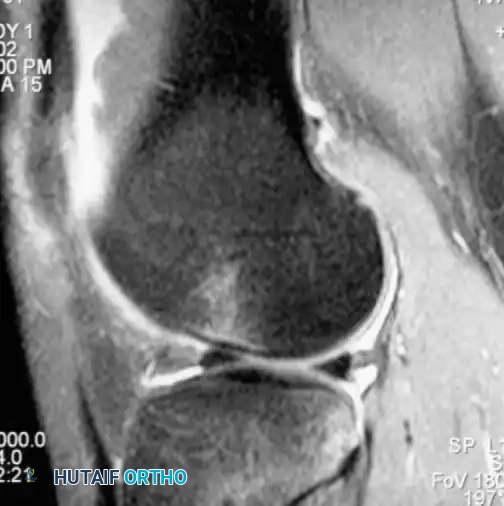

Magnetic Resonance Imaging (MRI):

MRI is the gold standard advanced imaging modality, with reported accuracies approaching 95% to 100%. Because the ACL courses obliquely, standard orthogonal sagittal planes may not capture the entire ligament.

RADIOGRAPHIC PEARL: Utilizing a nonorthogonal plane—achieved by externally rotating the knee approximately 15 degrees during the scan—allows for visualization of the entire ACL in a single continuous frame.

MRI is also highly sensitive for detecting associated bone bruises (microtrabecular fractures), which occur in up to 80% of acute ACL tears. These are typically located on the lateral femoral condyle and the posterolateral tibial plateau, reflecting the footprint of the pivot-shift mechanism.

Image

Fig. 43-102 Magnetic resonance image shows bone bruise after anterior cruciate ligament tear.

Associated Surgical & Radiographic Imaging

Hutaifortho's Orthopaedic Diagram